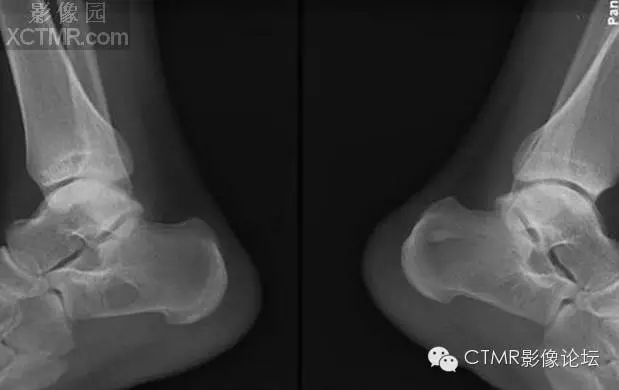

骨髓竇是指松質(zhì)骨內(nèi)先天性骨小梁發(fā)育稀少,各組骨小梁間的骨小梁少或缺如,形成一空腔,內(nèi)含有骨髓,稱為骨髓竇,為正常解剖變異。骨髓竇以跟骨最多見,簡稱骨髓竇,其次見于股骨頸、股骨遠端及髖臼上緣等處。

【臨床表現(xiàn)】

成人多見,因系解剖變異,無癥狀。常因外傷或其他原因做X線檢查時發(fā)現(xiàn)。

【X線表現(xiàn)】

1.跟骨竇的形成 跟骨示足弓的重要支點,承受著來自自身及負荷的重量。為了適應承受重量的力學需要,跟骨的結構十分精密合理。其骨小梁的發(fā)育有三組:①自跟距關節(jié)后緣向后下方呈斜向走行;②沿跟骨下方分布;③自跟結節(jié)處向前方伸展。三組骨小梁間有一個類三角形、圓形或橢圓形透亮區(qū),即跟骨竇。

2.跟骨竇的表現(xiàn) 觀察跟骨竇以側位平片為佳。其特點是位于跟骨前部中央,跟骨溝后方,尖端向上,足弓后上部,承受重量輕的特定位置。竇的基底與跟骨下緣平行。與竇基底相當?shù)母窍戮壠べ|(zhì)密度高,呈致密帶狀或線狀。竇內(nèi)骨小梁稀少或缺如。邊緣清楚整齊,無硬化。大小1-3cm。竇內(nèi)有時可見營養(yǎng)溝。多數(shù)為單側,少數(shù)雙側對稱發(fā)生。竇周骨質(zhì)正常。

【鑒別診斷】

1.跟骨囊腫 囊腫多位于跟骨后中部,與跟骨竇位置不同。呈圓形或橢圓形,囊內(nèi)無骨小梁,高度透亮,膨脹生長,周邊輕度硬化。

2.單房性巨細胞瘤 破壞區(qū)邊緣清楚,內(nèi)無骨間隔。骨皮質(zhì)變薄。臨床上有疼痛。腫瘤多位于跟骨后部,腫瘤中心多在跟骨竇之后。

3.跟骨結核 病變范圍較小,病變呈不規(guī)則破壞,邊緣模糊,無硬化,周圍骨質(zhì)疏松。

4. 骨內(nèi)脂肪瘤 骨內(nèi)脂肪瘤極罕見,多在長骨干骺。x光片見膨脹镕骨破壞,周邊光滑,有硬化緣,有時有鈣化灶,可誤診為骨梗死。病理:巨檢 黃色質(zhì)軟,脂肪祥,可鈣化或囊性變。

骨髓竇是指松質(zhì)骨內(nèi)先天性骨小梁發(fā)育稀少,各組骨小梁間的骨小梁少或缺如,形成一空腔,內(nèi)含有骨髓,稱為骨髓竇,為正常解剖變異。骨髓竇以跟骨最多見,簡稱骨髓竇,其次見于股骨頸、股骨遠端及髖臼上緣等處。X線表現(xiàn)邊緣清楚整齊,無硬化,大小1-3cm,病變區(qū)內(nèi)無鈣化,竇內(nèi)有時可見營養(yǎng)溝。竇周骨質(zhì)正常。